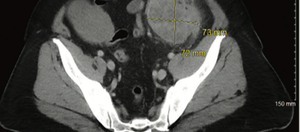

This case presents a patient with locally advanced, unresectable, mismatch repair–deficient sigmoid colon cancer who was treated with neoadjuvant chemoimmunotherapy followed by surgical resection leading to a complete pathologic response after preoperative systemic chemoimmunotherapy.